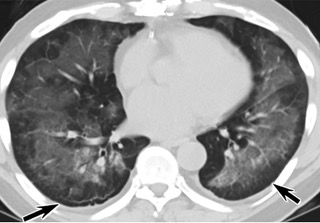

疑点一,电子烟患者的CT影像和临床表现并不具有特异性。所谓美国电子肺炎患者,其实是对没有其他合理诊断证据、吸食电子烟肺炎患者的统称。这些患者在病发前90天内吸食了电子烟,尤其值得注意的是,部分患者的CT影像特征和临床表现与病毒性肺炎患者极其相似。

疑点二,中国科研工作者从60篇研究论文中筛选出142位电子烟肺炎患者的250张影像图片,邀请3位放射科权威专家,对上述全部影像图片、相关病人临床信息以及文献原文进行了仔细全面研究与审查,又有了新的发现。

16位被文献报道为电子烟肺炎的患者被专家判定为“病毒性感染”,即有可能是新冠肺炎的“疑诊患者”,其中更有5位临床症状和治疗情况相对完整的患者被判定为“中度可疑”。因此在2019年美国报道的电子烟肺炎中存在病毒性感染的病例,而且不排除美国电子烟肺炎中存在新冠肺炎的可能性。